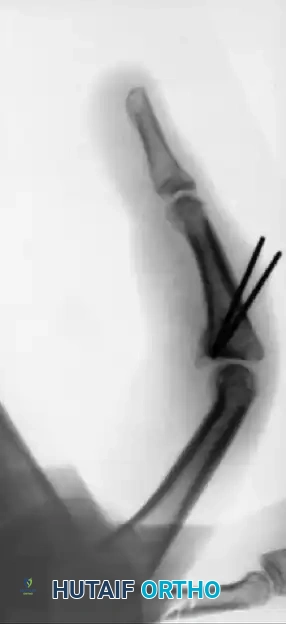

FIGURE 67-75: A, Malunited phalangeal fracture with rotational deformity. B, After treatment by osteotomy through the proximal end of the bone and fixation with two Kirschner wires. Healing is usually more rapid after osteotomy at this metaphyseal level than after one at the old diaphyseal fracture site.